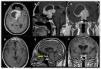

ResultsThe mean patient age was 48.17 ± 12.92 years. Vision loss was the most common presenting symptom (n = 20). Gross total resection (GTR) was achieved in 51.7% (n = 15) and subtotal resection (STR) in 48.3% (n = 14). Postoperative improvement in visual function was observed in 48.3% (n = 14), while 20.7% (n = 6) experienced deterioration. Endocrinological remission occurred in 20.7% (n = 6). Complications included diabetes insipidus (24.13%, n = 7), cerebrovascular events (10.34%, n = 3), and mortality (17.24%, n = 5).

ResultadosLa edad media de los pacientes fue de 48,17 ± 12,92 años. La pérdida de visión fue el síntoma más común (n = 20). Se logró una resección total macroscópica (RTM) en el 51,7% (n = 15) y una resección subtotal (RST) en el 48,3% (n = 14). La mejoría de la función visual postoperatoria se observó en el 48,3% (n = 14), mientras que el 20,7% (n = 6) experimentó deterioro. La remisión endocrinológica ocurrió en el 20,7% (n = 6). Las complicaciones incluyeron diabetes insípida (24,13%, n = 7), eventos cerebrovasculares (10,34%, n = 3) y mortalidad (17,24%, n = 5).